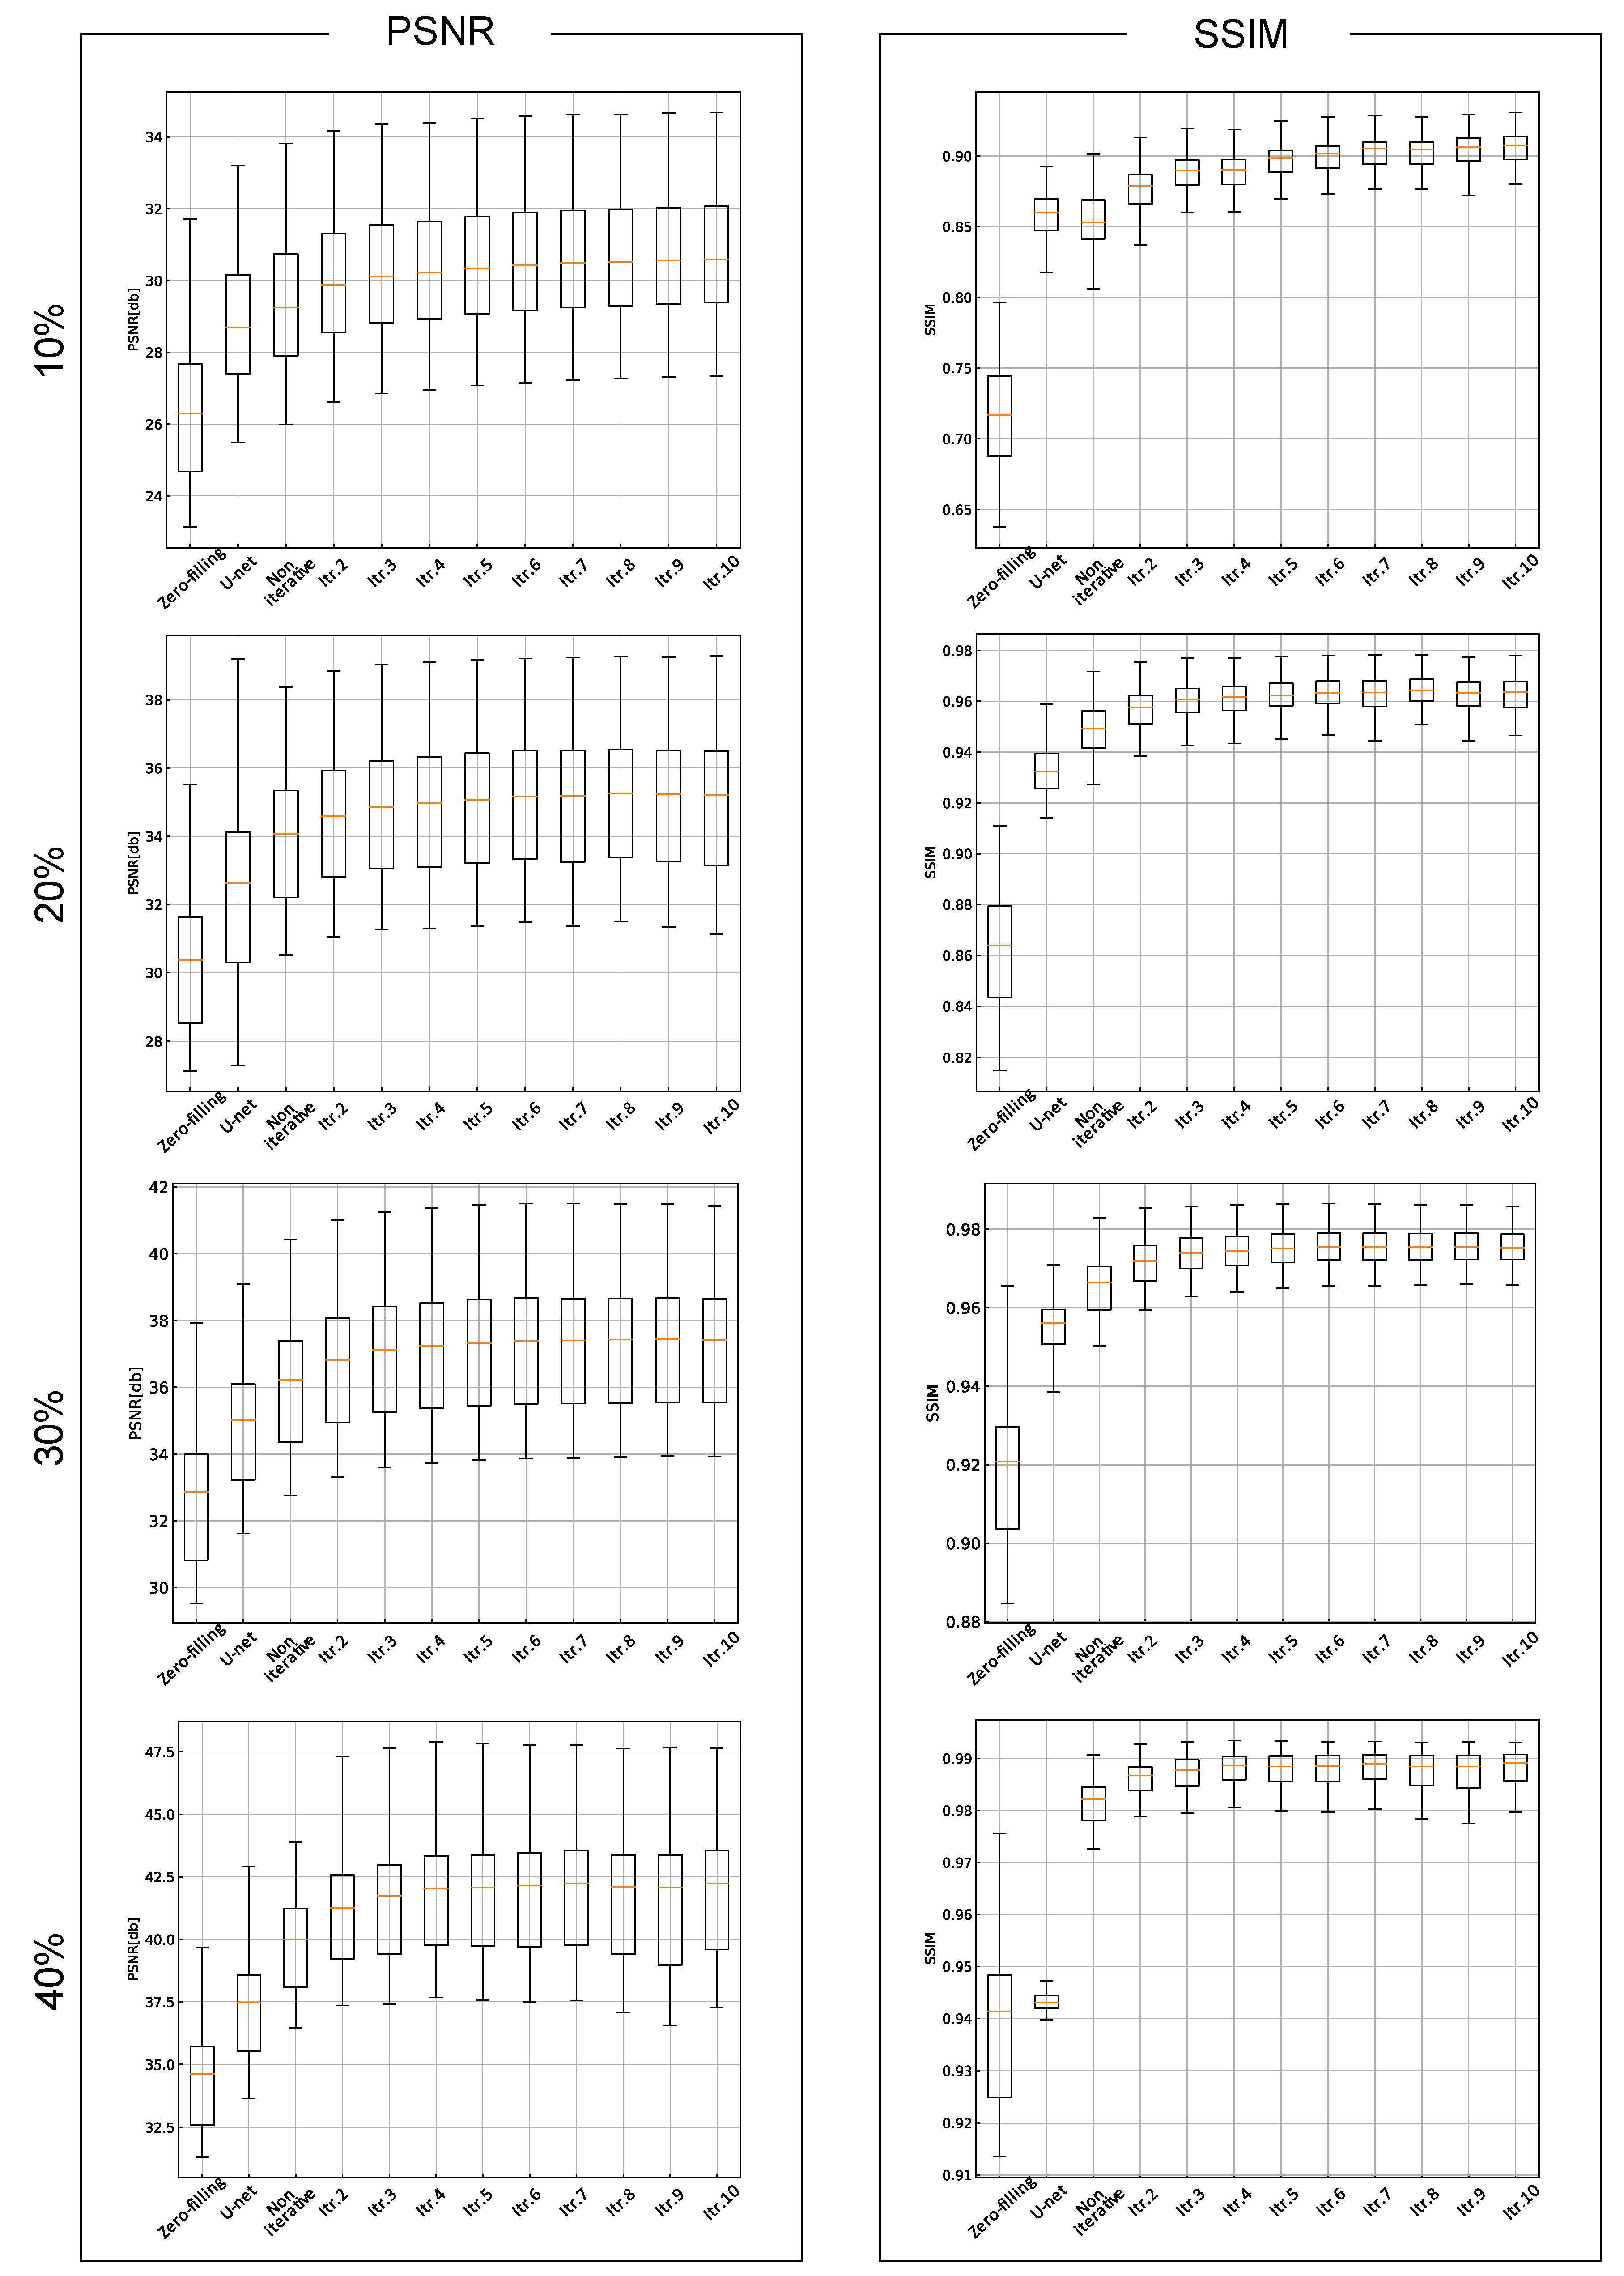

3. Results